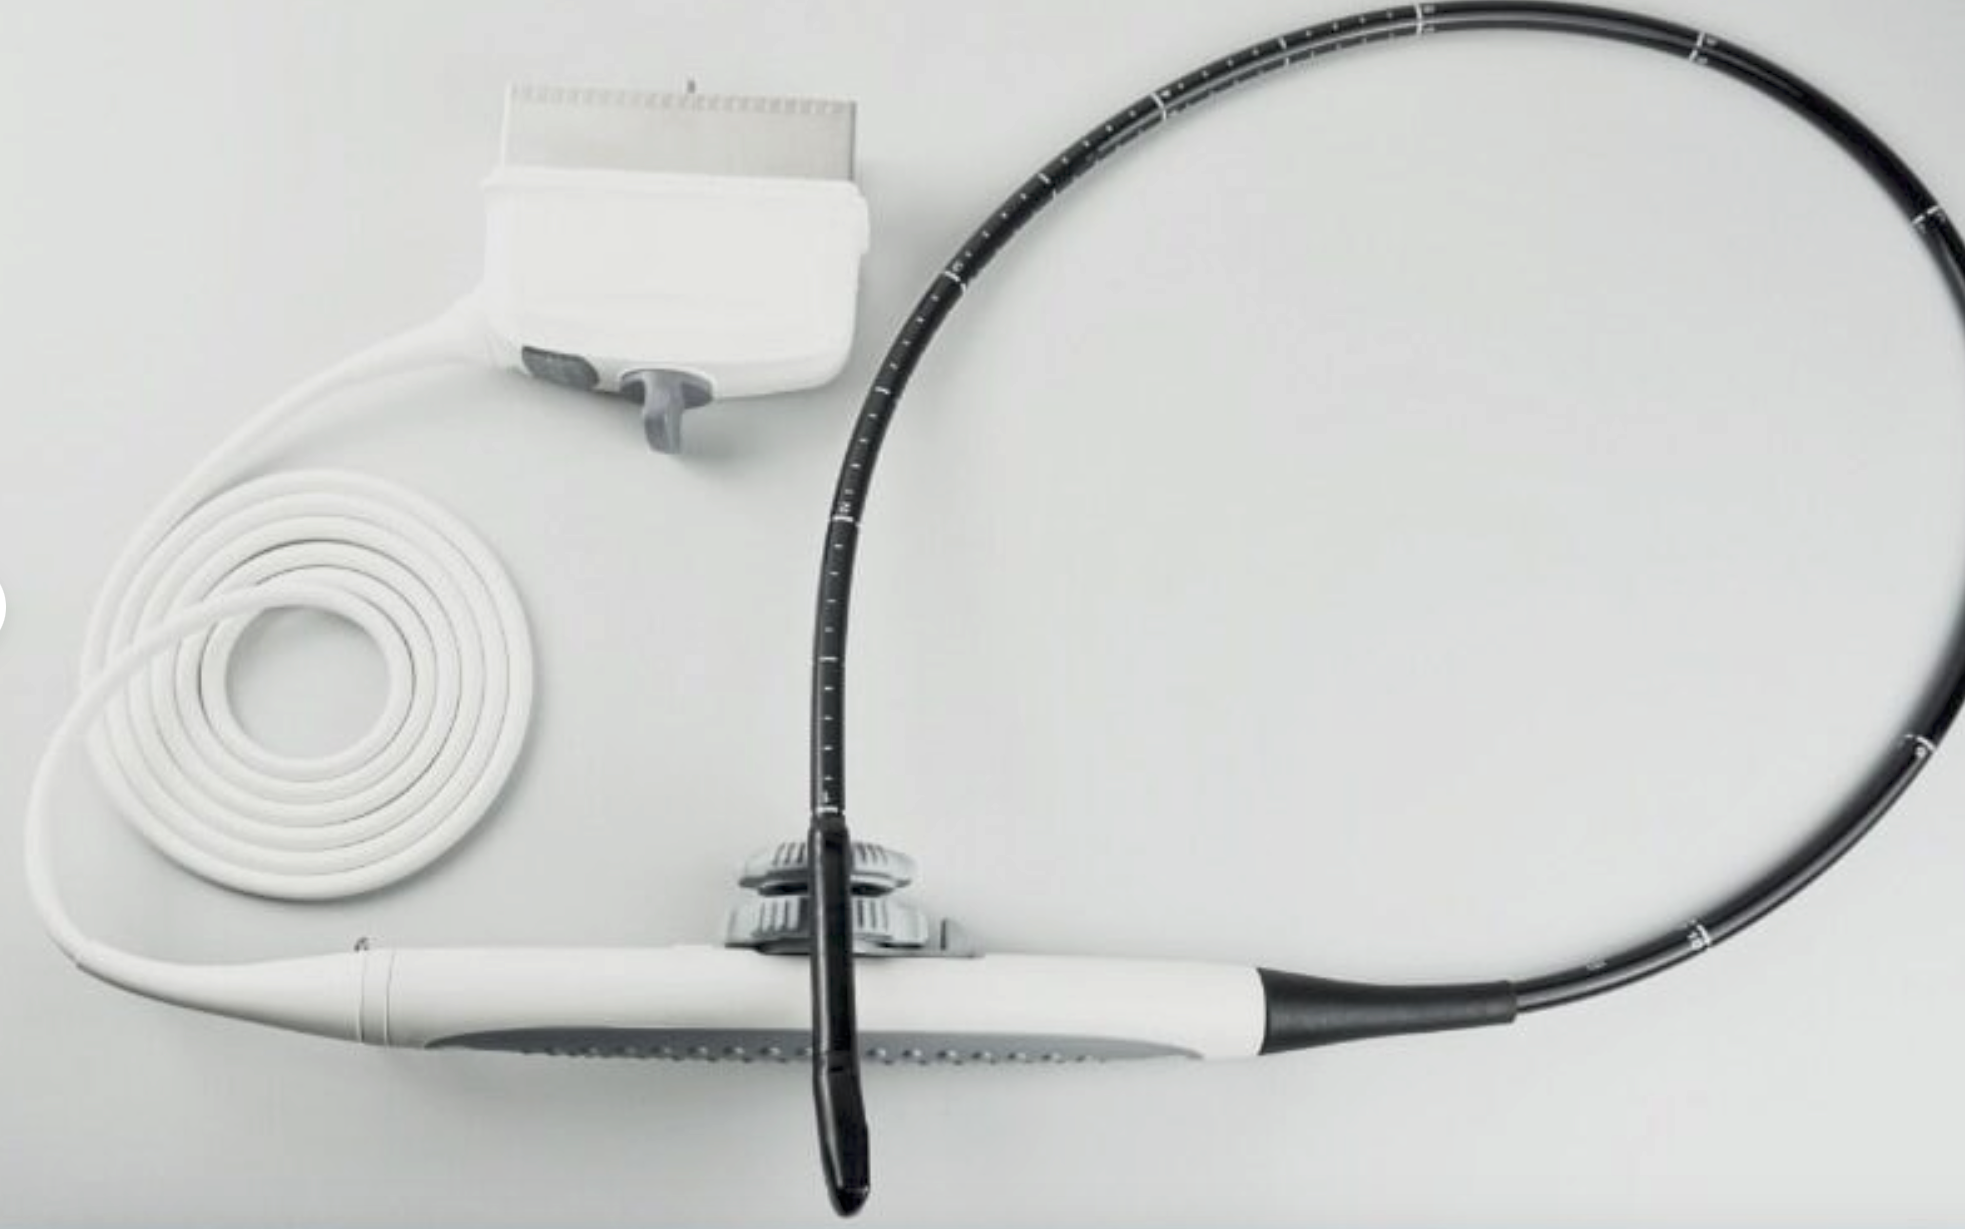

Philips X5-1 Explora Ultrasound Transducer

Sale price$ 45,572.30